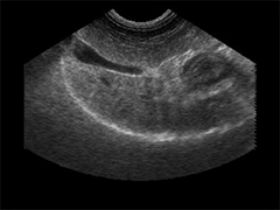

אבן בכיס מרה

כליה